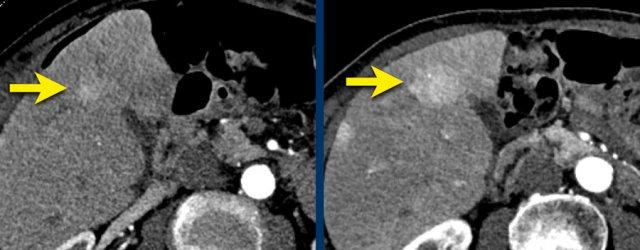

Đây là hình ảnh thì động mạch muộn của một bệnh nhân xơ gan.

Ghi nhận một tổn thương có tăng ngấm thuốc không dạng viền (mũi tên vàng).

Ở thì muộn, tổn thương có hiện tượng washout.

Đây là những đặc điểm điển hình của HCC.

Tổn thương còn lại (mũi tên xanh lá) là tổn thương đã được điều trị, sẽ được thảo luận ở phần sau.